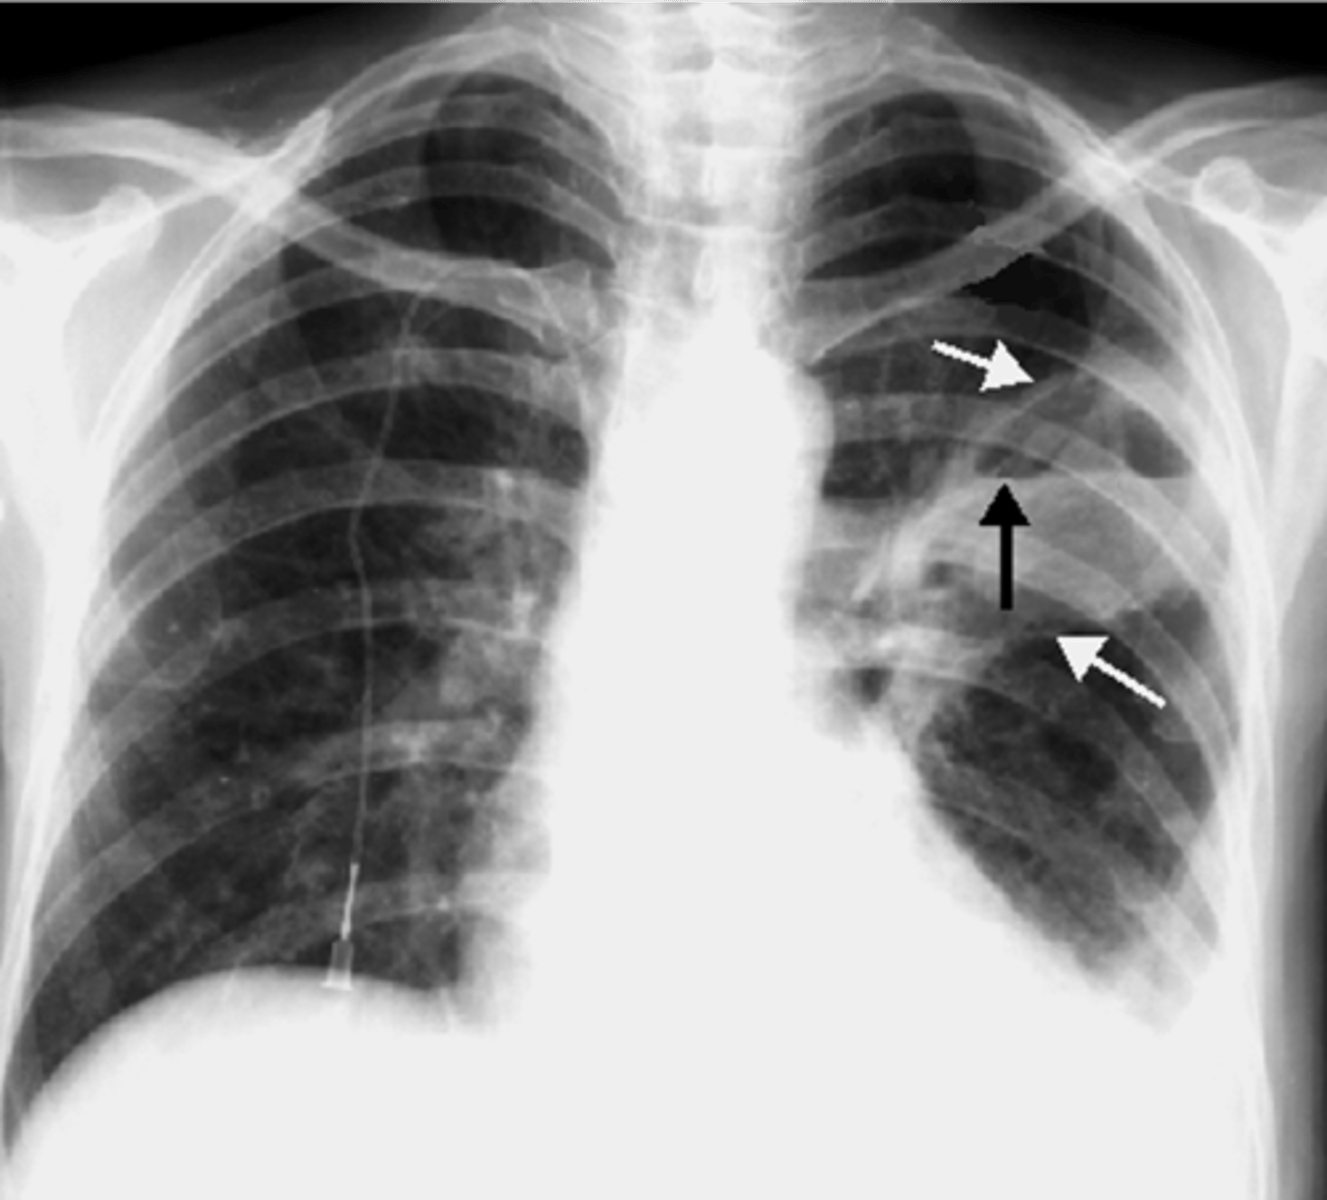

Silhouette sign right cardiac border- RML infiltrate

Silhouette sign right cardiac border, RML